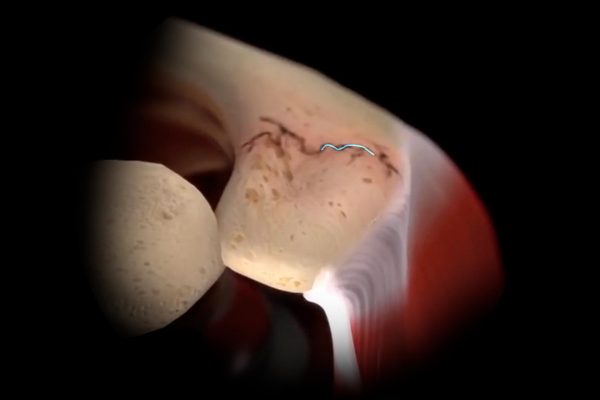

Review of Acromial and Scapular Fractures After Reverse Shoulder Arthroplasty: Inlay vs. Onlay Component Designs

Study of 3,018 reverse shoulders finds no strong link between inlay or onlay designs and risk of acromial or scapular fractures.